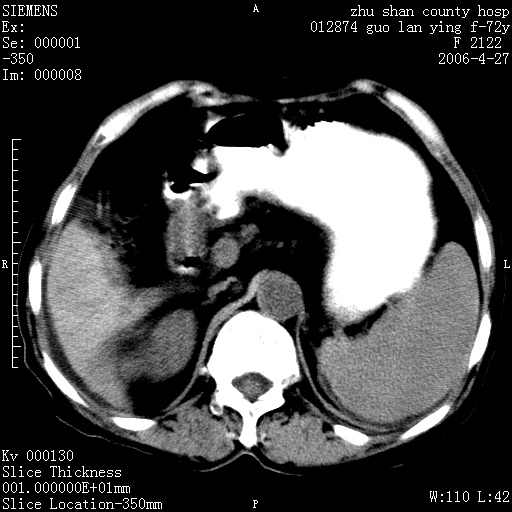

平扫所见:胆囊区两点壮高密度影,灶周有伪影{请问楼主患者有手术病史?}。肝实质内未见明显异常{建议强化或mri}.腹腔有少量积液,脾明显增大.右肾形态似不规则?

腹腔内示积液征,脾脏略增大,肝脏由于运动伪影较多,影响观察,内未见明显高密度区,胆囊内示两处高密度结石。胃窦部壁轻度增厚。另外,肝脏的前缘似有游历气体。不知病人的临床如何?有必要做胃的检查,还有,看看骨窗是否有腹腔游离气体还是肠管影响的。

肝脏缩小,脾脏增大,肝脾外缘及胆囊窝液性密度影,肝脾ct值正常,胆囊区见两个类圆形高密度影,下腔静脉前方类圆形软组织密度影为肝脏岛叶,胃幽门区见软组织密度影,十二指肠钡剂充盈不好.

1:腹水2:胆囊结石3肝硬化?(不确定,请结合临床)4幽门区占位?(建议胃肠透视)

肝硬化,脾大,少量腹水

肝硬化、腹水、脾大,胆囊结石可以肯定。只是肝右叶两个低密度有必要增强确定一下;排除小肝癌。